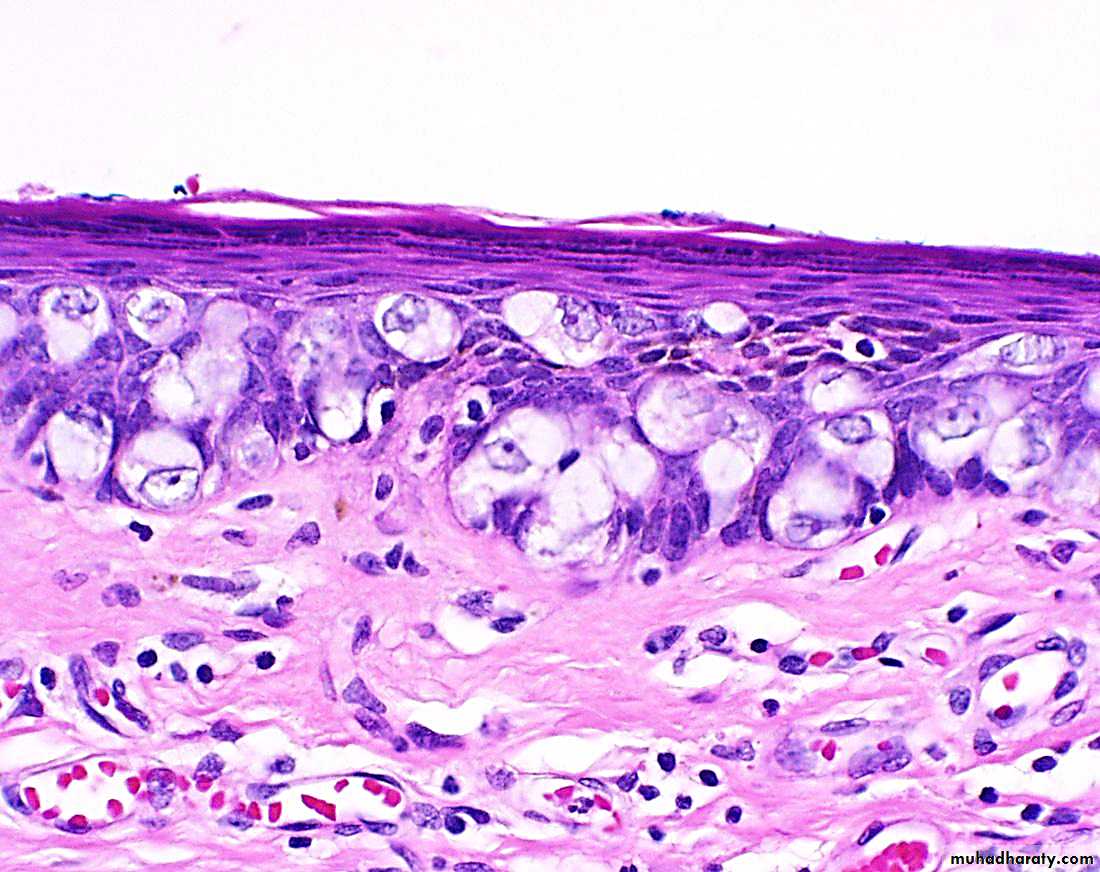

Histologically The papillary projections consist of fibrovascular stoma lined by stratified squamous epithelium with perinuclear vacuolisation called koilocytosis, indicative of HPV infection.

Condyloma acuminatum. Low-power view showing exophytic, papillary architecture.

High-power view reveals HPV cytopathic effect (koilocytic atypia) characterized by atypical, enlarged, hyperchromatic nuclei with perinuclear halos (arrow).Premalignant and Malignant Neoplasms: